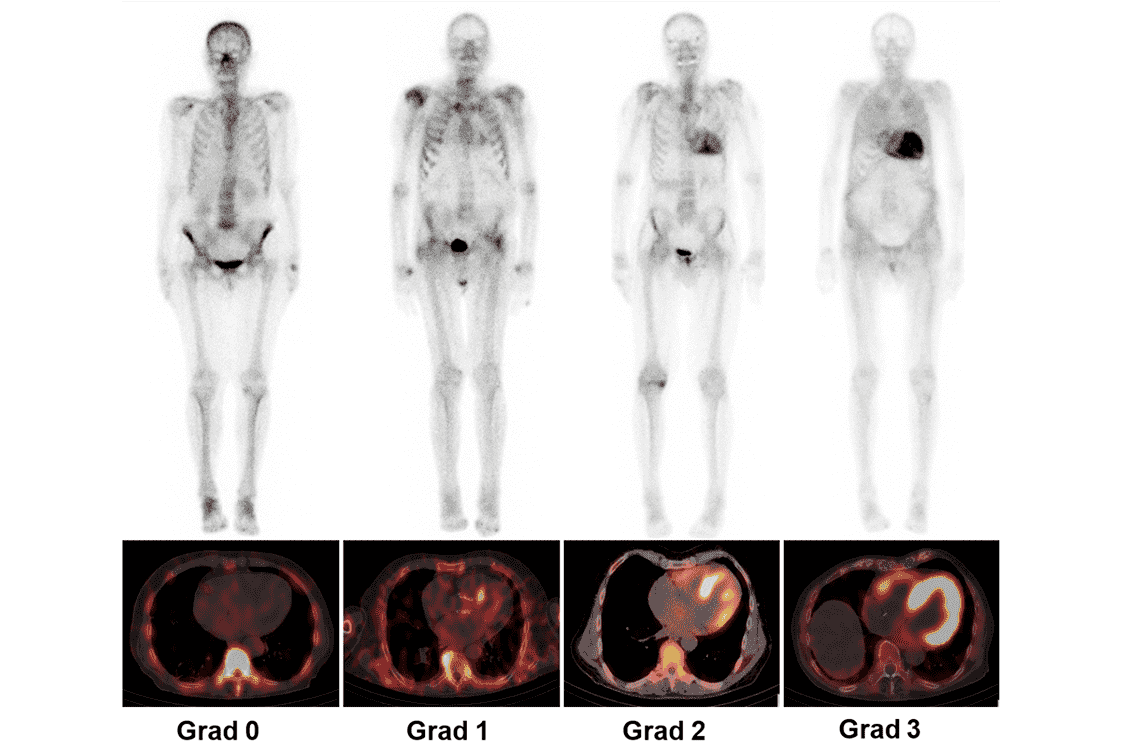

*99mTc-HMDP-Szintigrafie ist ebenfalls möglich.6